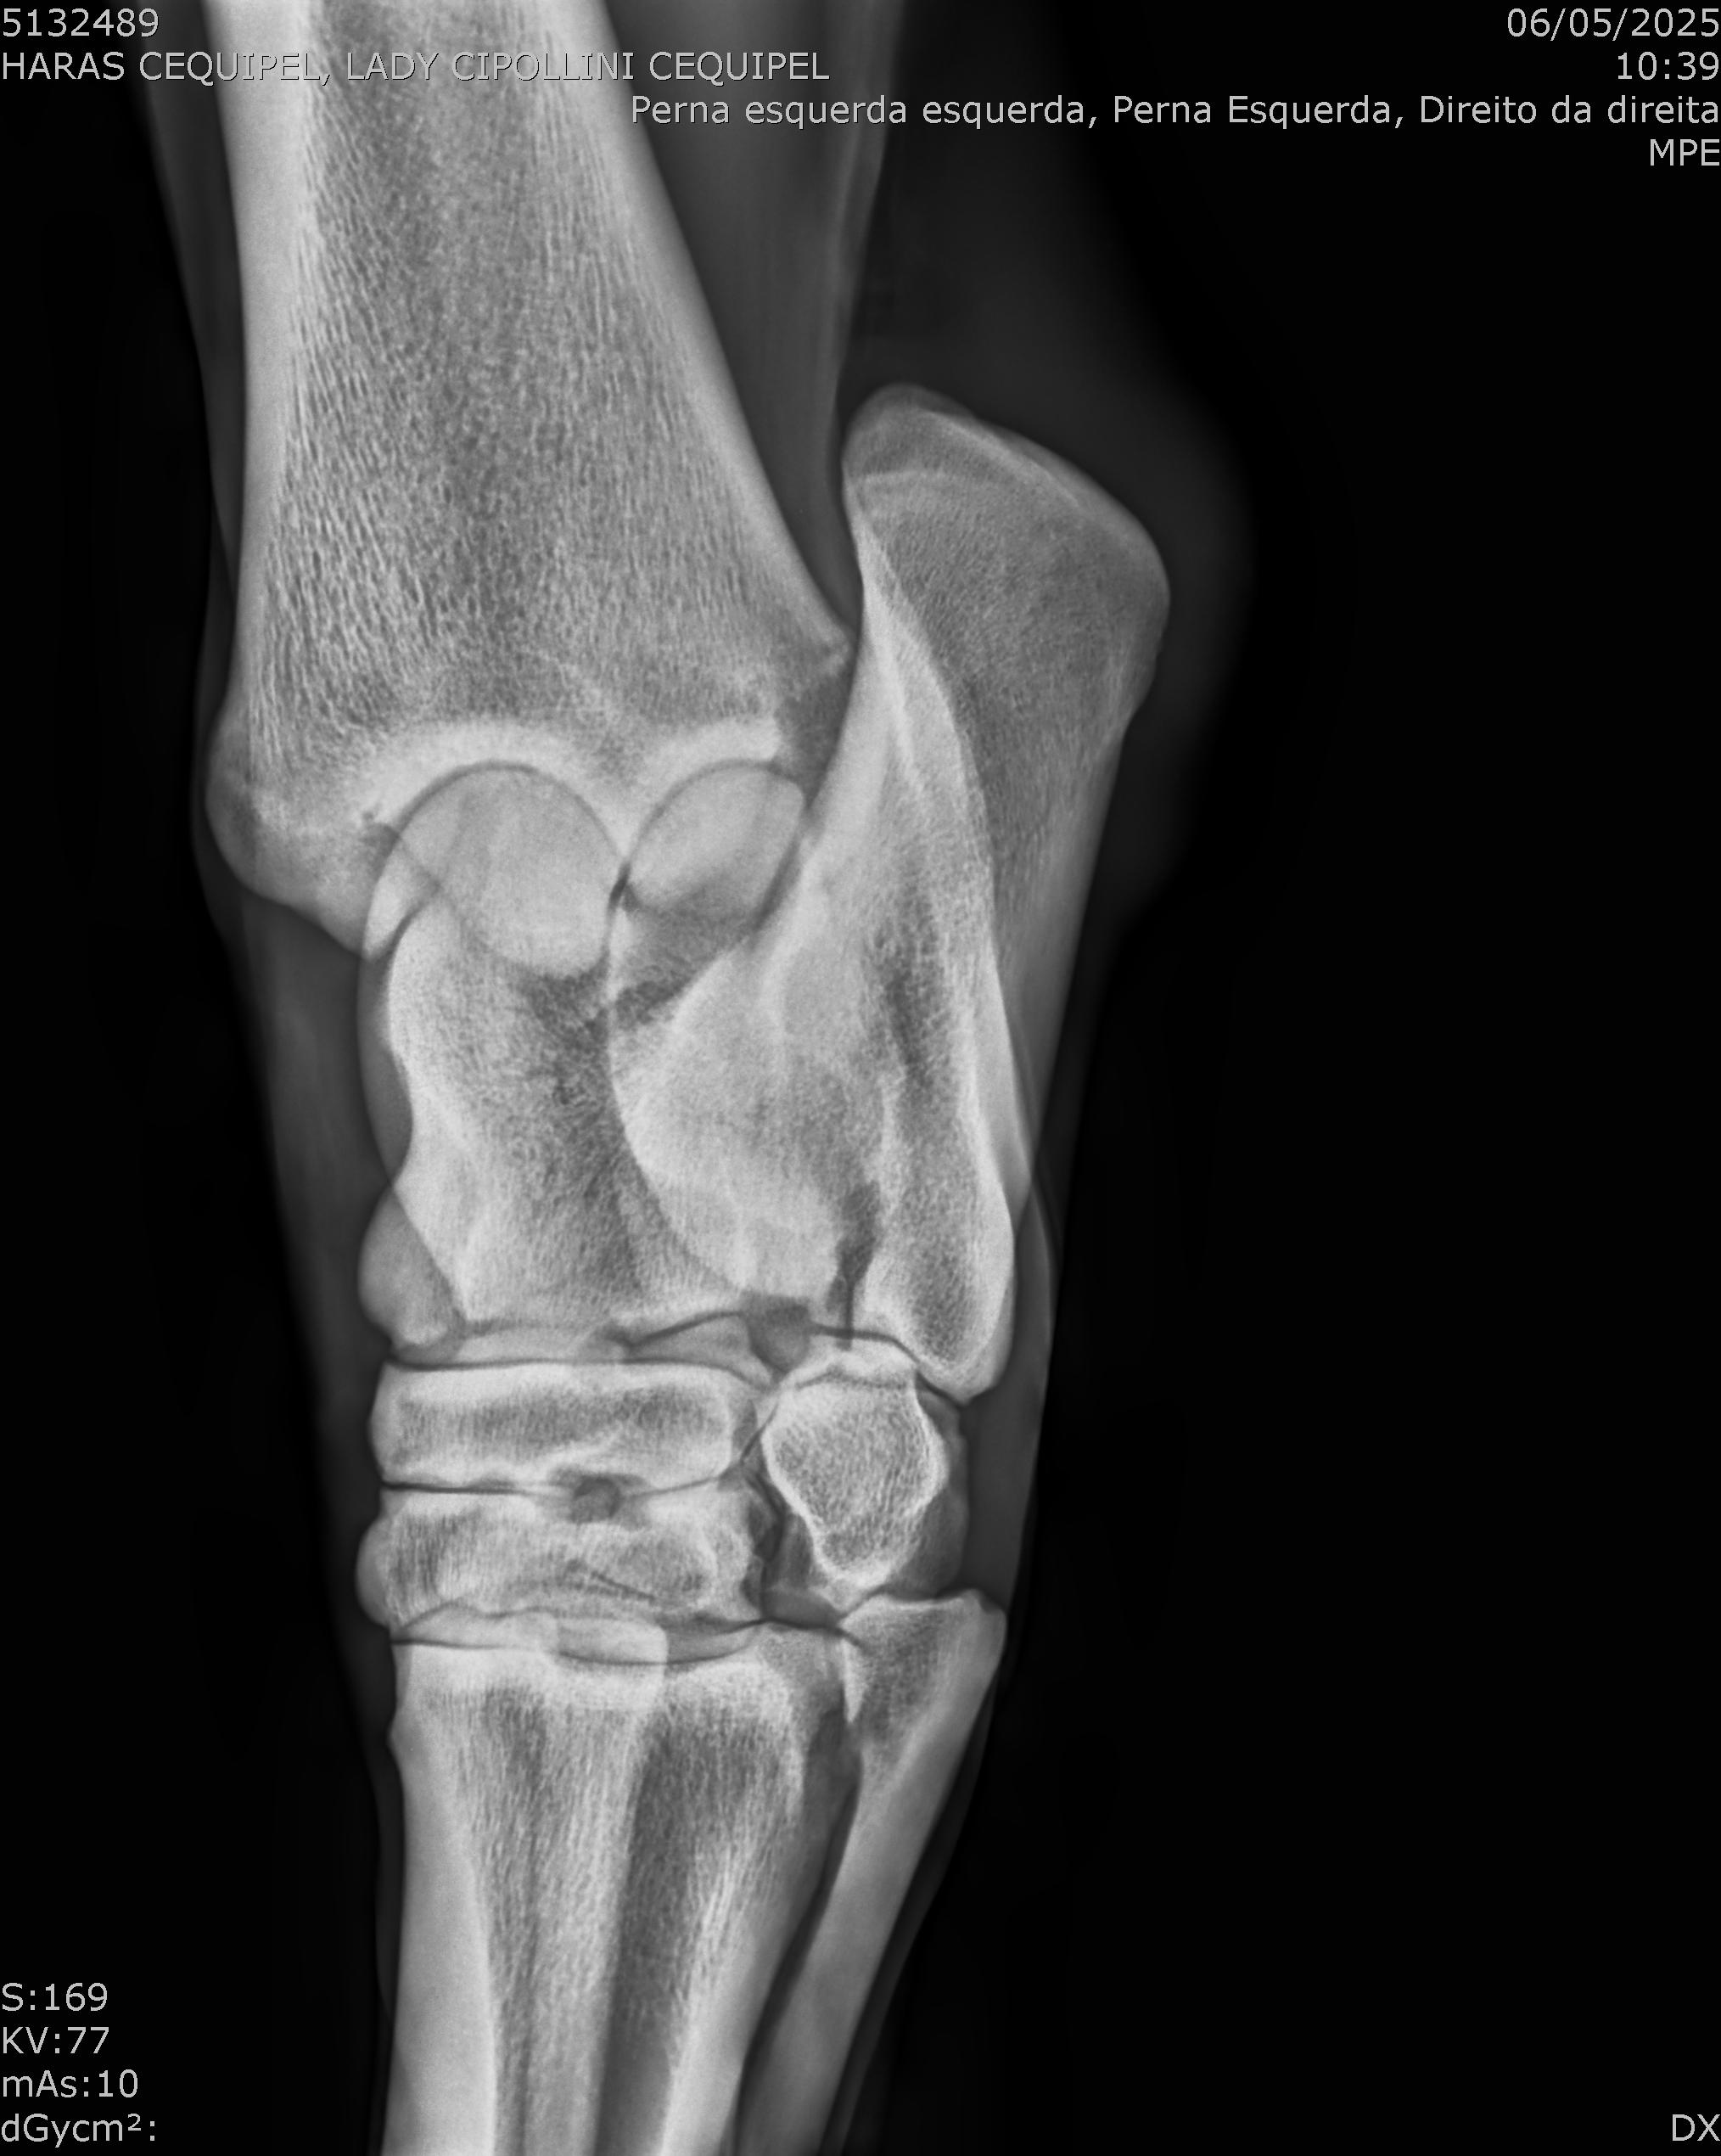

:: RAIOS-X DO LOTE